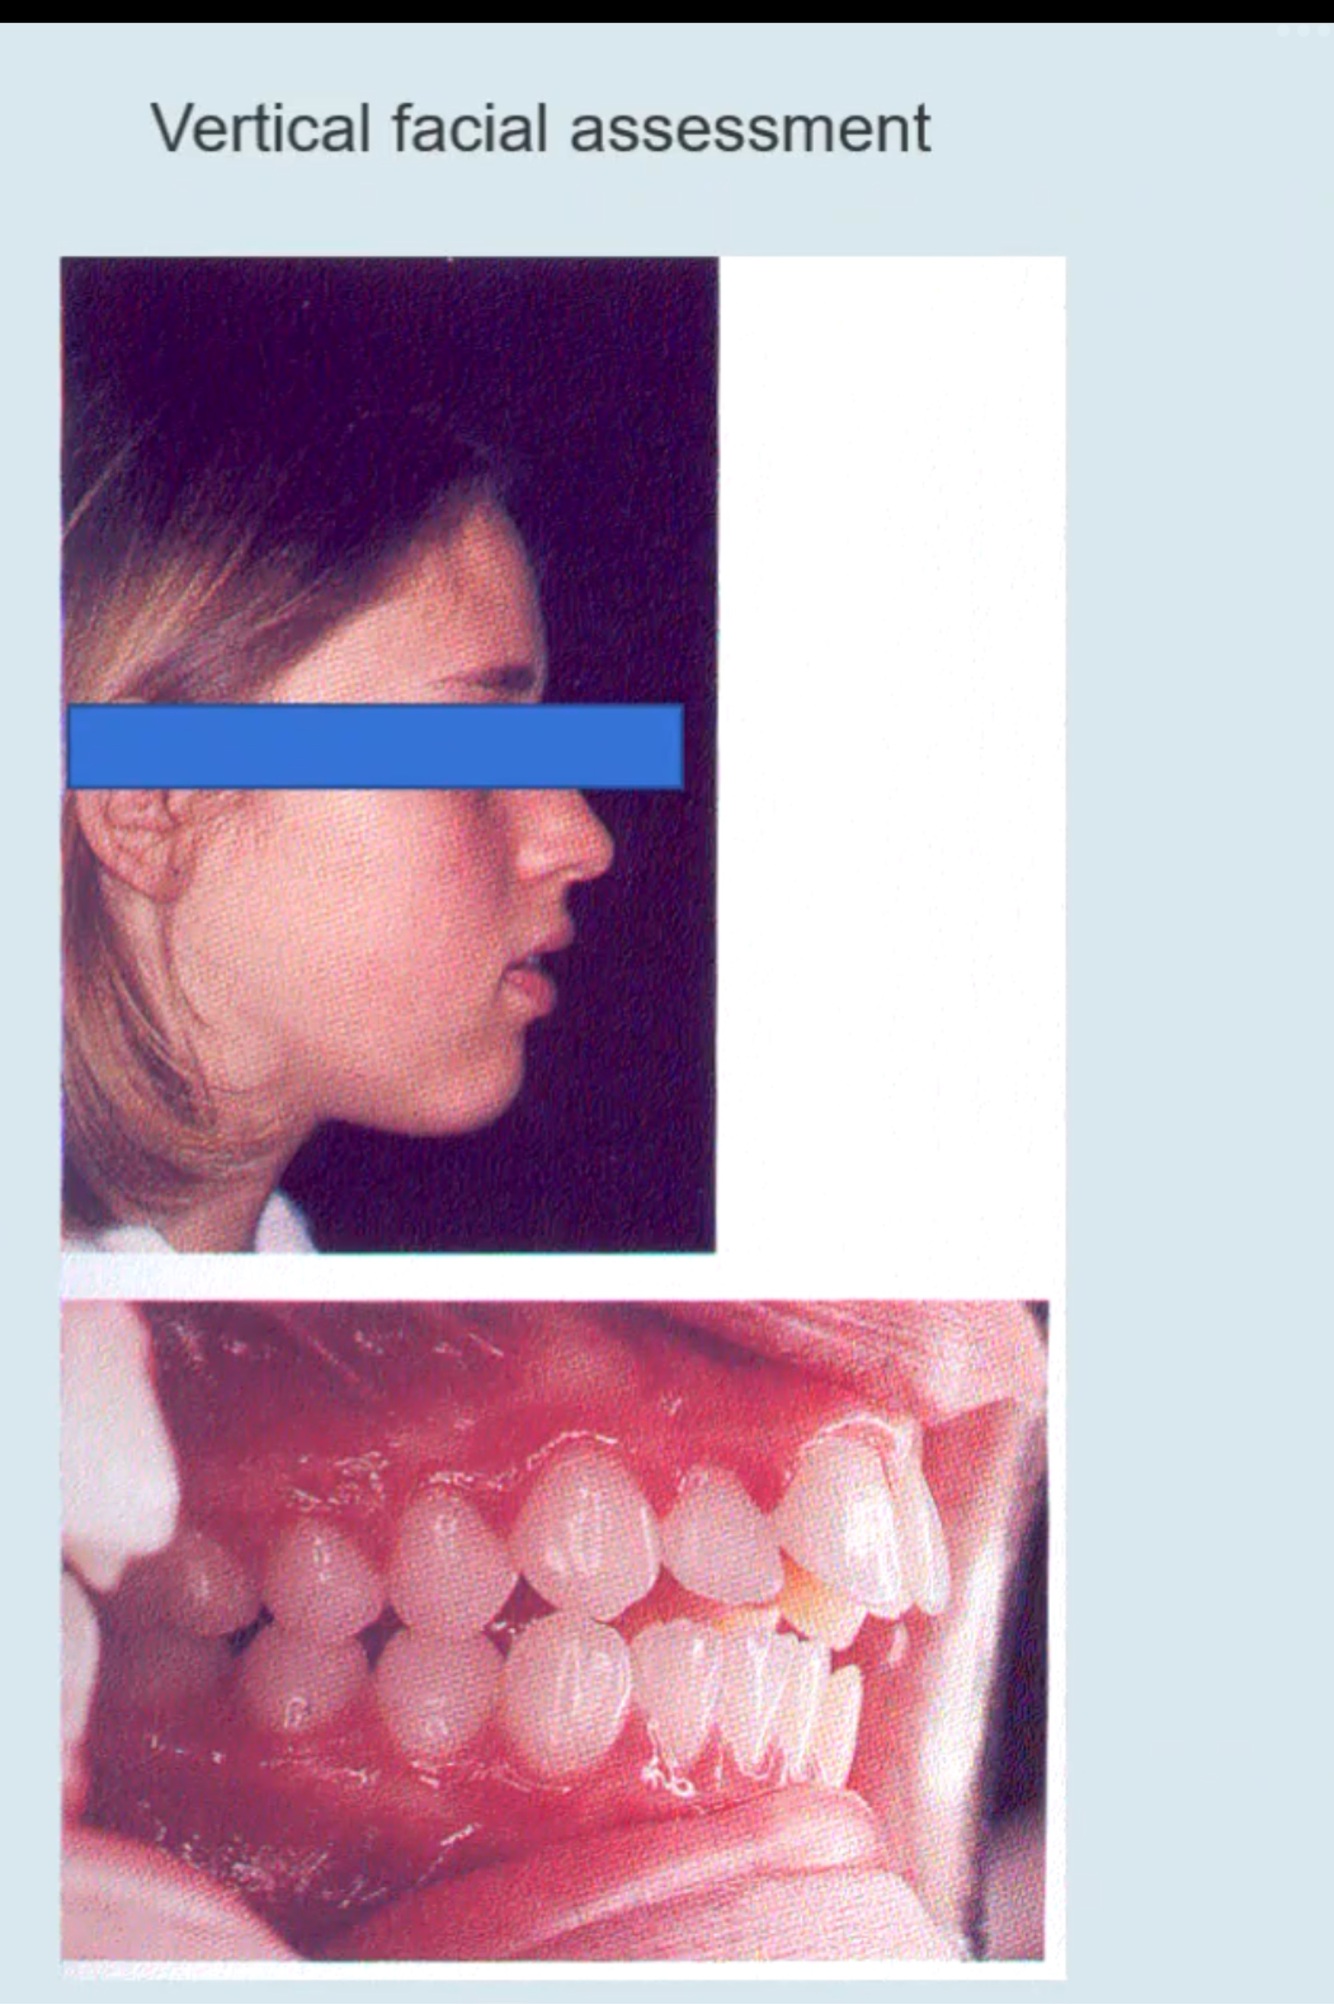

Skeletal vertical assessment

What 2 things do we check?

Increased vertical dimension leads to:

Decreased vertical dimension leads to:

A

Check frankforts mandibular plane angle + Lower face height

How are skeletal vertical facial assessments carried out ?

Vertical assessments done from a point called Glabella (most prominent point between the eyebrows) to a point called Subnasale (below the nose) to soft tissue menton

Clinically pt should have 50% between Glabella and subnasale and 50% between subnasale and soft tissue menton to have a well balance face - as shown below:

For this patient

If we assess this patient in vertical dimension - Frankfort mandibular plane angle and lower face height - mild skeletal 2 when we look at her profile

There’s an increase in vertical proportions between subnasale and soft tissue menton

So intraorally we are not suprised to see she has increase in overjet and there’s a reduced incomplete bite (DIFFERENT to anterior open bite)